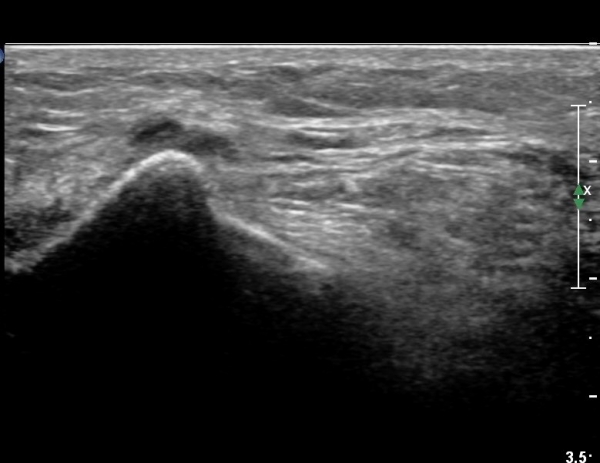

ŽÃËÀÚ¸¦ Á» ´õ ¸»´Ü, ¿ÜÃøÀ¸·Î À̵¿ÇÏ´Ï ºñ°ñµÎ Ç¥Ãþ¿¡¼­ ºñ°ñ½Å°æÀÌ Àú¿¡ÄÚ·Î °üÂûµÈ´Ù(»çÁø 3, 4, 5).